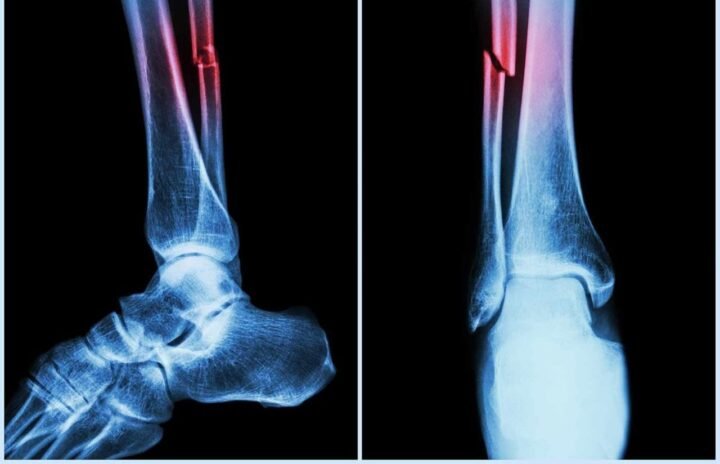

आप फुटबॉल खेल रहे हैं, पैर मुड़ा, तेज़ दर्द और फिर वही पुरानी कहानी एक्स-रे, प्लास्टर, महीनों की बेड़ियाँ, चलने की जद्दोजहद…

चीनी वैज्ञानिकों ने एक ऐसा लिक्विड बायो-कम्पैटिबल गोंद विकसित किया है जो टूटी हड्डियों को महज़ 2 से 3 मिनट में जोड़ सकता है।

इस गोंद को टूटी हुई हड्डी के दो सिरों के बीच लगाया जाता है, और फिर कुछ ही मिनटों में यह इतना मज़बूत बंधन बना लेता है कि प्लास्टर या स्क्रू की जरूरत ही नहीं पड़ती।

इस तकनीक का नाम फिलहाल “Tissue-Adhesive Liquid Bone Glue” बताया जा रहा है और इसे खास तौर पर ह्यूमन बोन टिश्यू के साथ कंपैटिबल बनाने पर फोकस किया गया है।